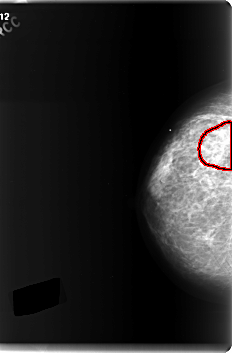

C_0183_1.RIGHT_CC

RIGHT_CC LINES 5992 PIXELS_PER_LINE 3944 BITS_PER_PIXEL 12 RESOLUTION 50 OVERLAY

FILE: C_0183_1.RIGHT_CC.OVERLAY

TOTAL_ABNORMALITIES 1

ABNORMALITY 1

LESION_TYPE MASS SHAPE IRREGULAR MARGINS ILL_DEFINED

ASSESSMENT 3

SUBTLETY 1

PATHOLOGY MALIGNANT

TOTAL_OUTLINES 1

BOUNDARY